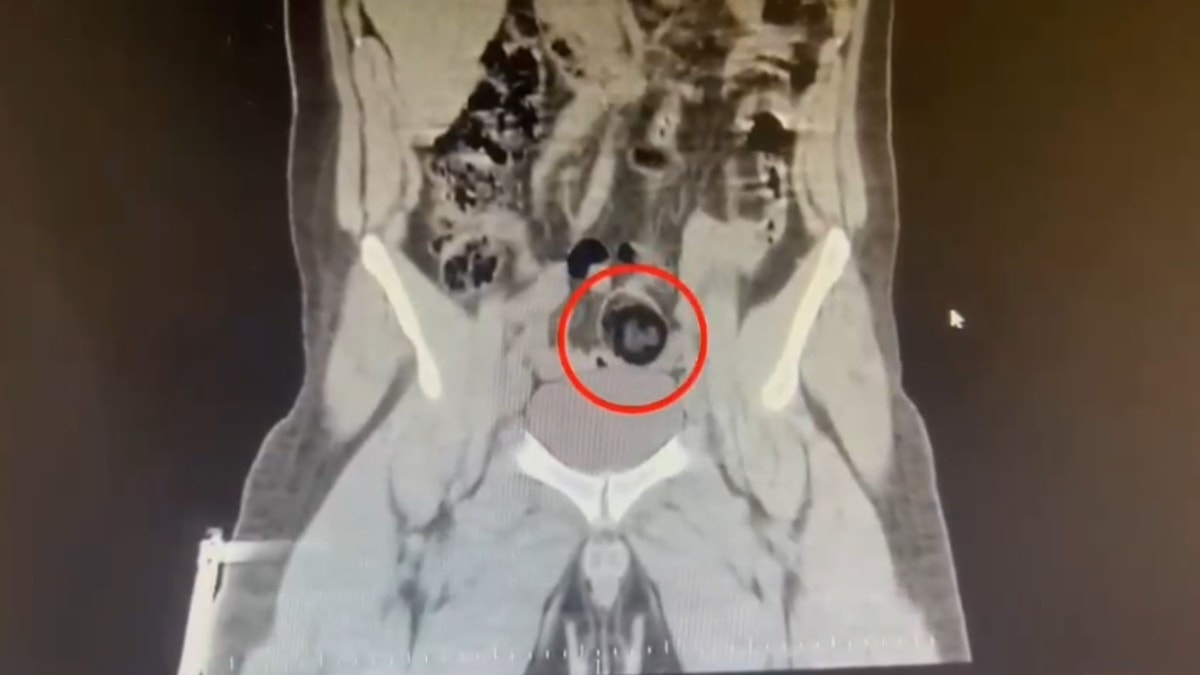

Şüpheli hareketler sergileyen kuryenin, götürüldüğü hastanede yapılan iç beden muayenesinde makatında cisim olduğu anlaşıldı.

Kuryenin makatındaki 105,98 gram metamfetamin, gerçekleştirilen cerrahi müdahaleyle çıkarıldı.